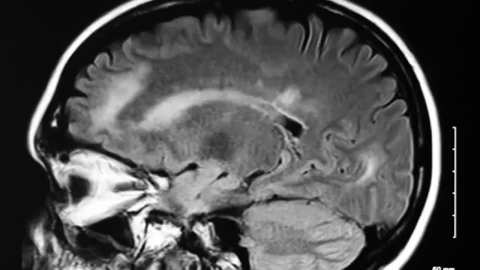

Tham vọng "sửa chữa" não người của tỷ phú Elon Musk

Elon Musk vừa ra mắt phiên bản mới nhất của giao diện não Neuralink vào tháng trước. Theo ông, trầm cảm, nghiện, đột quỵ, tổn thương não… tất cả đều có thể giải quyết nhờ Neuralink. Liệu điều này có khả thi?